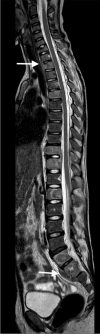

Tuberculosis (TB) remains one of the major public health threats worldwide, despite improved diagnostic and therapeutic methods. Tuberculosis is one of the main causes of infectious disease in the chest and is associated with substantial morbidity and mortality in paediatric populations, particularly in low- and middle-income countries. Due to the difficulty in obtaining microbiological confirmation of pulmonary TB in children, diagnosis often relies on a combination of clinical and radiological findings. The early diagnosis of central nervous system TB is challenging with presumptive diagnosis heavily reliant on imaging. Brain infection can present as a diffuse exudative basal leptomeningitis or as localised disease (tuberculoma, abscess, cerebritis). Spinal TB may present as radiculomyelitis, spinal tuberculoma or abscess or epidural phlegmon. Musculoskeletal manifestation accounts for 10% of extrapulmonary presentations but is easily overlooked with its insidious clinical course and non-specific imaging findings. Common musculoskeletal manifestations of TB include spondylitis, arthritis and osteomyelitis, while tenosynovitis and bursitis are less common. Abdominal TB presents with a triad of pain, fever and weight loss. Abdominal TB may occur in various forms, as tuberculous lymphadenopathy or peritoneal, gastrointestinal or visceral TB. Chest radiographs should be performed, as approximately 15% to 25% of children with abdominal TB have concomitant pulmonary infection. Urogenital TB is rare in children. This article will review the classic radiological findings in childhood TB in each of the major systems in order of clinical prevalence, namely chest, central nervous system, spine, musculoskeletal, abdomen and genitourinary system.